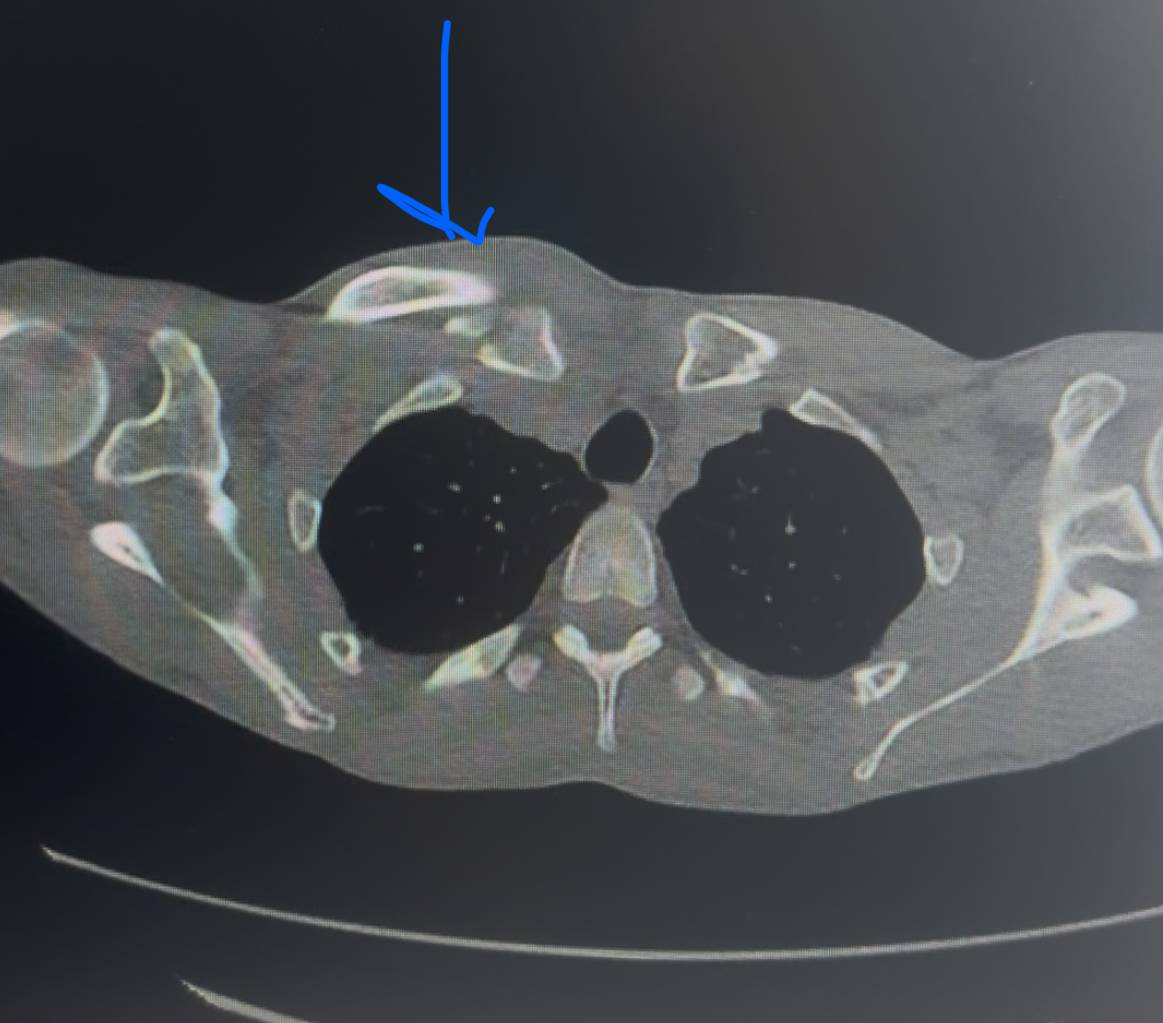

Fractured collarbone, laceration above my eye, ambulance ride to the hospital.

Within this whole process with Leo, my collarbone was not healing correctly, so I decided to have surgery to repair it. This restarted a healing process and rehabilitation. Something I'm continuing to work on today, more than 5 months after the initial injury. Everything is getting better, but progress is usually never as fast as you want it to be.